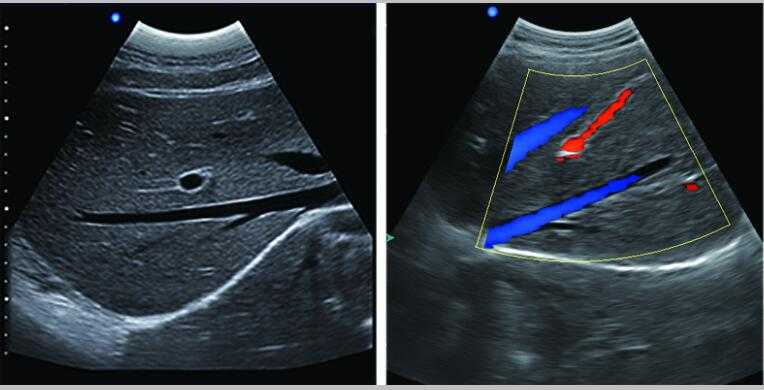

L3-VET筆記本式獸用B超機

L3-VET便攜筆記本式獸用B超機適用探頭